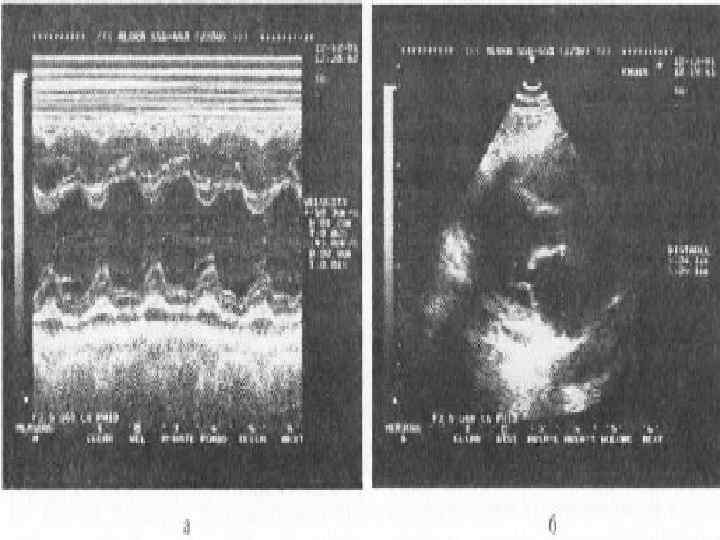

При тампонаде правые отделы сердца очень чувствительно реагируют на фазы дыхания. • На вдохе кровенаполнение правых отделов увеличивается, что приводит к увеличению их диастолических размеров • На выдохе, наоборот, приток крови к правым отделам уменьшается, давление в них падает до уровня давления в перикарде и ниже • Это приводит к коллабированию правого предсердия и желудочка, что проявляется инвагинацией (прогибанием внутрь) их свободных стенок

• В то время как правые отделы на выдохе спадаются (коллабируют), левый желудочек увеличивается. Эти реципрокные изменения приводят к pulsus paradoxus. • Механизм увеличения размеров левого желудочка: напряженный выпот в полости перикарда оставляет ограниченное пространство для кровенаполнения сердца, в результате при уменьшении объема правого желудочка (на выдохе) левый желудочек увеличивается и, наоборот, при увеличении правого желудочка (на вдохе) левый желудочек уменьшается.

• Если при М-модальном исследовании правого желудочка субкостально на уровне чуть ниже атриовентрикулярного отверстия выявлено уменьшение его полости менее чем до 1 см, то это должно вызвать сильные подозрения на тампонаду сердца

• При начинающейся тампонаде сердца увеличение давления в полости перикарда препятствует наполнению правого желудочка и, следовательно, нормальному коллабированию нижней полой вены. • Это первый признак развивающейся тампонады сердца: недостаточное коллабирование нижней полой вены появляется еще до спадения правых отделов сердца на выдохе.

• Коллабирование нижней полой вены после глубокого вдоха составляет менее 50%. • Имеется сильная связь между давлением в правом предсердии и поведением нижней полой вены. • При коллабировании ее менее, чем на 50%, указывает на то, что давление в правом предсердии превышает 10 мм рт. ст. ,